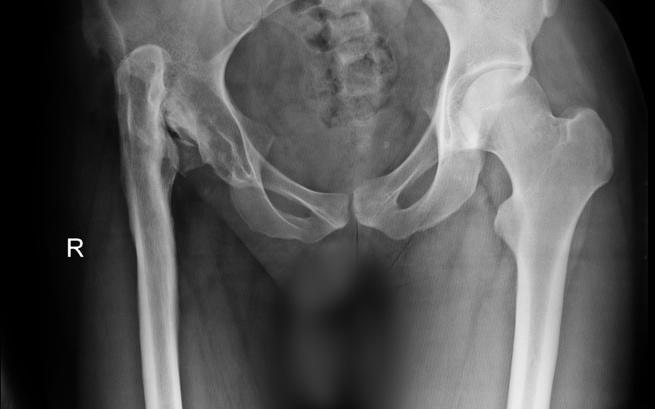

Urodziłem się jako zdrowe dziecko, a lekarze przyznali mi 9 punktów w skali Apgar. Niestety zaledwie kilka godzin później zostałem zakażony gronkowcem złocistym! Bakteria zaatakowała moje ciało, szczególnie cały staw biodrowy, panewkę i główkę kości udowej. Już jako mały chłopiec musiałem przejść pierwsze skomplikowane operacje, dzięki którym mogę dziś chodzić. Jednak to był dopiero początek... Wraz z upływem lat ograniczał się zakres ruchu mojego stawu biodrowego, a do tego na każdym kroku towarzyszył mi wielki ból. Dlatego szukałem każdej formy pomocy! Przeszedłem też kolejne operacje, ale wiem, że jeszcze nie ostatnie. Dlatego tak bardzo potrzebuję stałego wsparcia wielu specjalistów, dalszego leczenia i intensywnej rehabilitacji.